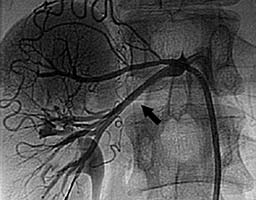

После дилятации суженной артерии. Просвет артерии полностью восстановлен (черная стрелка). |